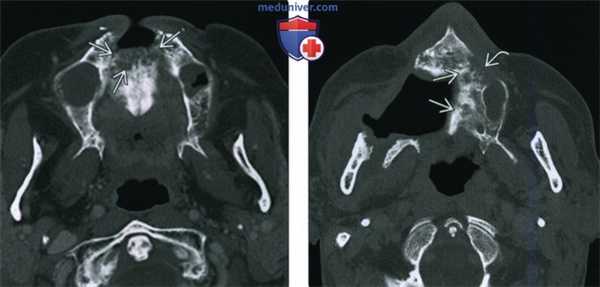

(Слева) При аксиальной КТ в коаном окне определяется патологическая мягкая ткань, заполняющая левый наружный слуховой канал (НСК) и ячейки сосцевидного отростка с явной деструкцией задней стенки ВСК и перегородок в сосцевидном отростке. Обратите внимание на смешанные склеротические и литические изменения костей - типичный вид височной кости при остеорадионекрозе.

(Справа) При аксиальной КТ в костном окне определяется радиационно-индуцированный некроз костного НСК и сливная деструкция ячеек сосцевидного отростка. Обратите внимание на «плавающий» костный секвестр. Все изменения указывают на тяжелый остеорадионекроз.

(Слева) При аксиальной КТ в костном окне определяется диффузное снижение пневматизации среднего уха и сосцевидного отроака в сочетании с пермеативно-деструктивными изменениями костей у пациента, подвергшегося ранее облучению. Определяется фокальный некроз пирамиды и латеральной кортикальной пластинки сосцевидного отростка.

(Справа) При аксиальной МРТ Т1 С+ FS у пациента, подвергшегося ранее облучению, определяется неспецифическая ткань, накапливающая контраст, в среднем ухе, сосцевидном отростке и вершине пирамиды. Лучевые изменения костей можно заподозрить на МРТ, но для заключения об ОРН лучше всего подходит КТ височных костей.